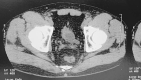

Results: Patient 1: A 58-year-old female had five episodes of acute left ureteral lithiasis in two years prior to left kidney tuberculosis. Patient 2: A 55-year-old male patient had a 1.2 cm proximal left ureteral stone and in the following six months, the diagnosis of tuberculosis was made in a nonfunctioning left kidney with ureteral thickening and stenosis. Patient 3: A 47-year-old male patient had a 1.2 cm stone in the proximal right ureter and developed urinary tuberculosis with a nonfunctioning right kidney and a contracted bladder.